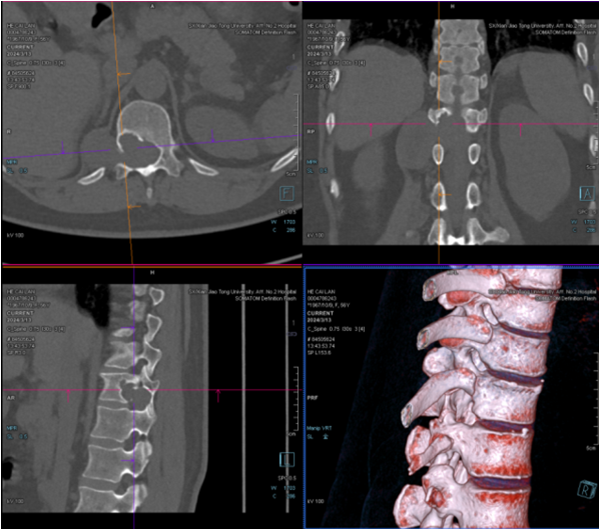

在患者及家属的全力支持与配合下,手术由王栋主任主刀,秦杰副主任医师、李京主治医师和邹宇佳规培医师协助,麻醉科李芳组长、牛晓莉副主任医师实施麻醉,手术室赵丽燕护士长、古茹副护士长和胡佩莹护士的配合协助。手术过程中,发现肿瘤呈不规则形,向椎管内、腹膜后、椎管后方等多个方向生长,最大直径近12cm。团队成功实施了胸椎椎管内占位切除术和胸椎椎弓根钉内固定术,完整切除了肿瘤既解除了脊髓所受的压迫,又重建了脊柱的稳定性。术后,科室与康复医学科紧密合作,为患者制定了个性化的康复治疗计划,并在骨二科李珂护士长、陈静副护士长和崔凤主管护师的精心指导下进行康复锻炼。

近一个月来,骨科中心脊柱与骨肿瘤病区已成功完成多例脊柱占位的复杂手术。通过术前详细检查,制定个性化的治疗方案,结合术中脊柱导航辅助技术,手术团队在精细操作中有效缩短了手术时长,减少了术中出血,显著改善了神经压迫症状,提高了患者的生活质量,延长了患者的生命。这些成功的案例不仅彰显了我院骨科中心脊柱与骨肿瘤病区的高超医术和团队协作精神,更为众多脊柱与骨肿瘤患者带来了希望。